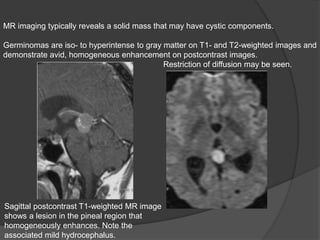

MR imaging typically reveals a solid mass that may have cystic components.

Germinomas are iso- to hyperintense to gray matter on T1- and T2-weighted images and

demonstrate avid, homogeneous enhancement on postcontrast images.

Restriction of diffusion may be seen.

Sagittal postcontrast T1-weighted MR image

shows a lesion in the pineal region that

homogeneously enhances. Note the

associated mild hydrocephalus.